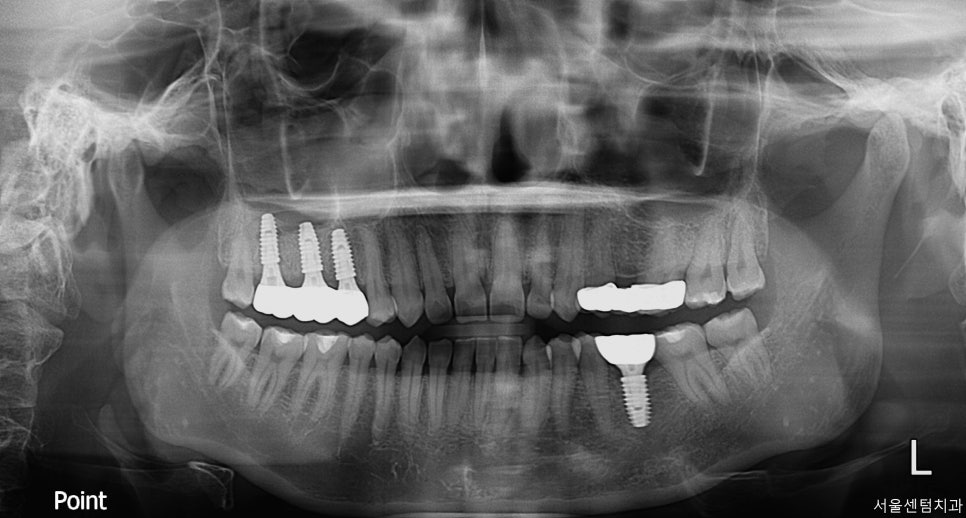

최종보철 수복 및 완료

드디어 이 긴 치료의 마지막 단계

최종 크라운을 제작하고

장착을 하는 과정인데요.

이 단계에서는 여러가지를 체크를 해야합니다.

최종보철시 위 아래의 치아가 편안하게

맞물리게 되었는지

옆 치아와 자연스럽게 닿는지

색상과 형태가 자연스러운지

방사선으로 최종확인까지 해야합니다.

최종완성 4개 부위 임플란트 모두 성공적으로 마무리

최근 현재까지 임플란트 주위에 골 소실 없이

안정적인 예후를 보여주고 계신데요.

BEFORE / AFTER